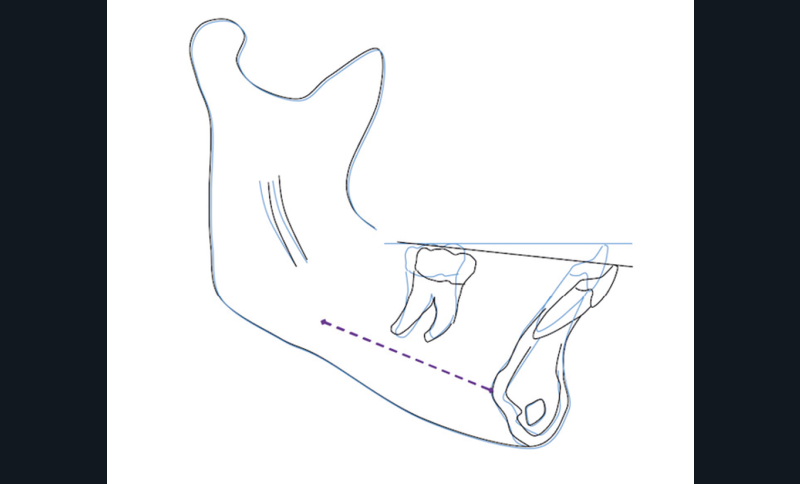

Nous équipons la patiente avec un appareil multi-attaches (.022 x .028 inch pré-informé Roth) mais nous n’avons pas activé l’arcade mandibulaire. La patiente est adressée au chirurgien maxillo-facial (Dr Gonzague Deffrennes, hôpital Beaujon) qui réalise l’avulsion des troisièmes molaires et la pose de plaques vissées avec émergence entre les premières et deuxièmes molaires mandibulaires dans l’axe des brackets (fig. 9). Étant donné l’absence d’encombrement au niveau incisif mandibulaire, nous pouvons rapidement mettre en place les tractions postérieures. Nous solidarisons ainsi le bloc antérieur de canine à canine et réalisons un recul en masse de l’arcade directement des canines aux plaques postérieures. La majeure partie du recul est faite sur un arc acier .018x.025 inch permettant le glissement. La force appliquée est de 250-300 g par côté.

L’alternative aux plaques est de positionner une vis dans le trigone rétro-molaire, comme décrit dans l’article de Marinetti, A, Deffrennes et Soussan [2], mais nous avons choisi les plaques compte tenu des forces exercées et du taux d’échec des vis acceptable mais moyen retrouvé dans la littérature [3,4]. Les plaques sont fixées à distance des racines. L’émergence au niveau de la ligne mucco-gingivale permet de maintenir une bonne hygiène. Leur position permet un recul complet d’arcade de manière symétrique. Il est possible de tracter de manière indirecte avec une potence canine et une traction plus basse sur la plaque en se rapprochant du centre de résistance de l’arcade.